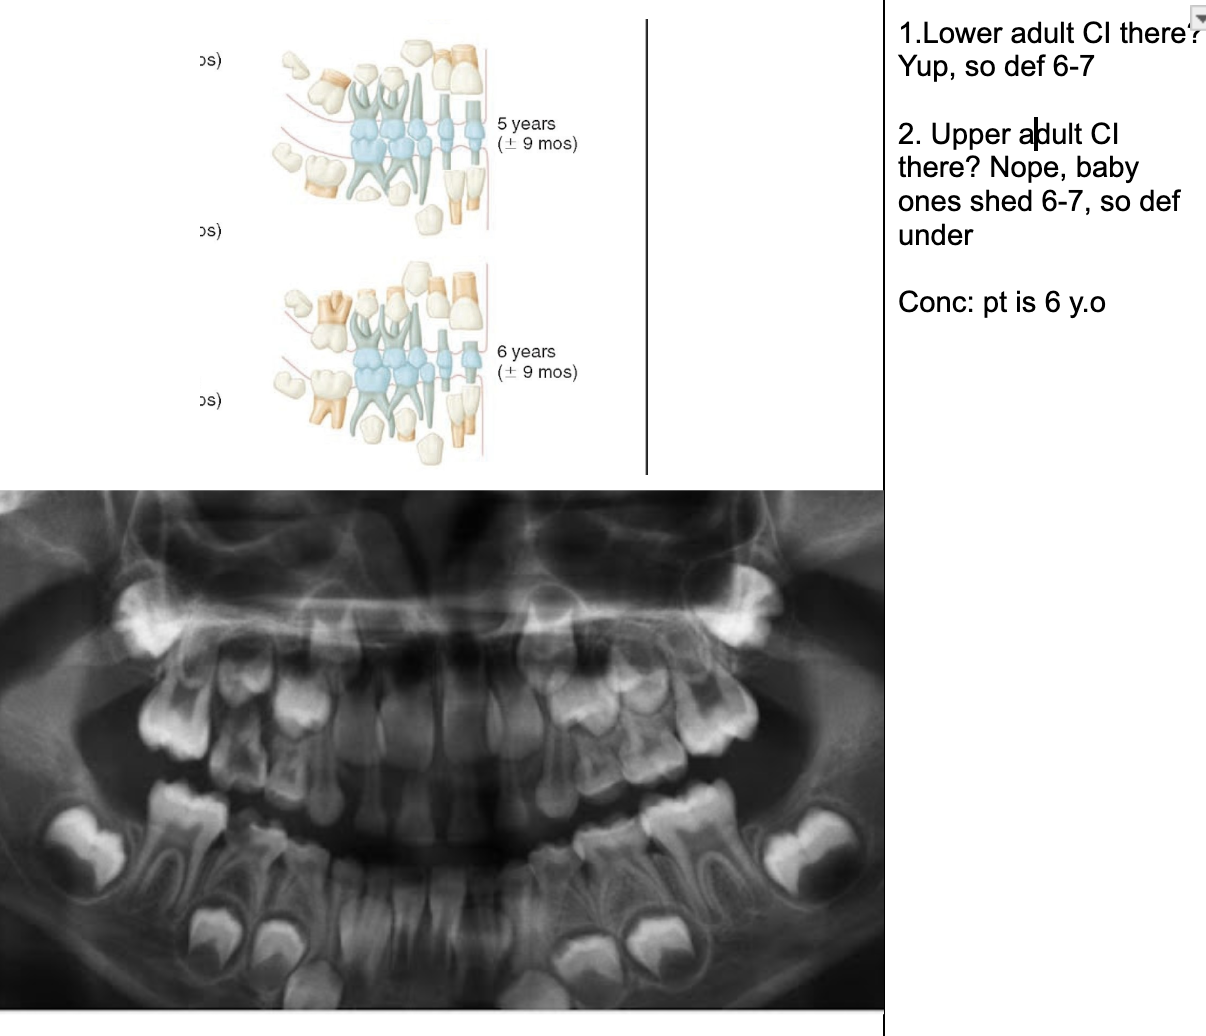

Permanent lower incisors present? Yes, so definitely 6-7

Permanent upper Incisors not erupted yet. Therefore not 7-8 y.o.

Conclusion = 6 y.o